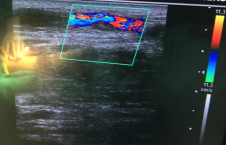

附图

(一) 暨南大学第一附属医院胡波博士指导超声引导下球囊扩张术

(三) 手术前后血管对比示意图